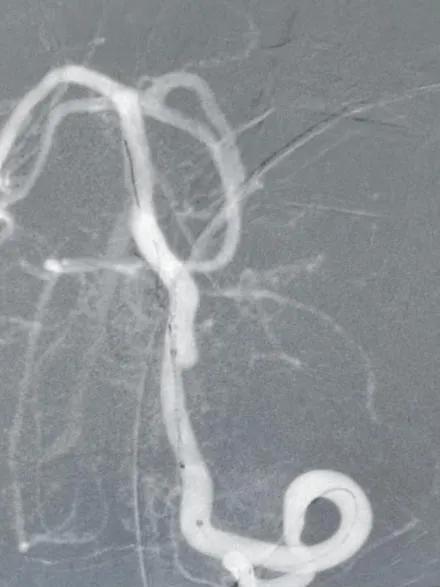

支架置入过程

术后图像

造影显示病变部位造影剂滞留。载瘤动脉通畅,脊髓前动脉通畅。后分别行左右颈内动脉及右侧椎动脉正侧位造影,未见明显血管异常。